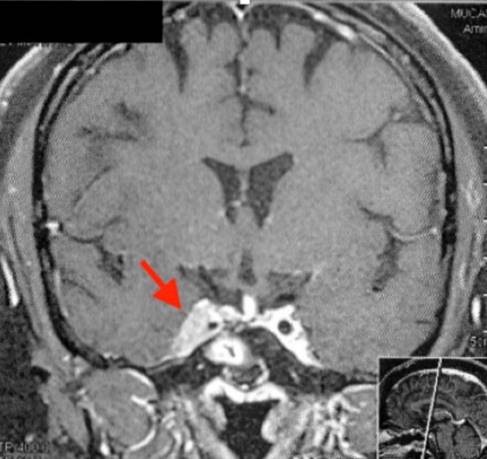

Paciente de sexo femenino, 27 años, derivada a nuestro servicio por EC recurrente y persistente. El cuadro clínico inicial es caracterizado por obesidad central, estrías rojo vinosas y debilidad muscular. Se realiza diagnóstico bioquímico de hipercortisolismo ACTH dependiente con un tumor hipofisario de 14 mm. Se realiza cirugía transesfenoidal y se confirma adenoma hipofisario secretor de ACTH (inmunohistoquímica: ACTH positivo, Ki 67 <2%). Mejoría clínica y bioquímica con normalización del cortisol libre urinario. En los 2 años siguientes, recidiva clínica, bioquímica y estructural. Se realiza segunda cirugía transesfenoidal. Al año siguiente, se documenta persistencia clínica, bioquímica (cortisol libre urinario CLU 252 µg/24 h, valor normal (VN) <50) y estructural de la enfermedad (adenoma hipofisario de 21 x 20 x 24 mm, con invasión del seno cavernoso). Se realiza radioterapia, 25 Grays en 5 fracciones en un total de 1,2 semanas. Luego de 6 meses se evidencia peoría clínica, se inicia ketoconazol 800 mg por día y cabergolina 0,5 mg por semana que se aumentan a 1.200 mg/ día y a 2 mg/semana, respectivamente. Hipertensión arterial en tratamiento con espironolactona; hipotiroidismo secundario en tratamiento con levotiroxina y amenorrea secundaria de 4 años de evolución. Tabaquista de 10 cigarrillos/día. De la evolución se destaca CLU en ascenso (figura 1) y la RMN sin cambios (figura 2). Además se evidencia aumento de enzimas hepáticas en más de 5 veces el VN, por lo cual se desciende dosis de ketoconazol hasta su suspensión. Peoría de los síntomas, con debilidad muscular proximal severa. Se realiza diagnóstico de diabetes mellitus tipo 2 y se inicia metformina. Valorada en ateneo se plantea AB dada la severidad del hipercortisolismo (CLU aproximado de 1.500 µg/24 h, cortisol sérico a la hora 8 AM mayor a 60 ug/dl más miopatía progresiva debilitante) y falla de los otros tratamientos. Se ingresa a la paciente a cuidados intensivos y se realiza una infusión de etomidato 0,05 mg/kg/h intravenoso durante las 48 h previas. Se logra buen control de la presión arterial y de la glicemia. Finalmente, con la paciente en oportunidad se realiza plan preoperatorio con la administración de hidrocortisona. Se procede a la AB. La suprarrenal derecha se extirpa por vía laparoscópica y la izquierda por laparotomía dadas las dificultades técnicas durante la cirugía, duración aproximada de 3 h. En las próximas 36 h posquirúrgicas instala disfunción orgánica múltiple, se procede a intubación orotraqueal y tratamiento con adrenalina y noradrenalina. A las 72 h presenta paro cardiorrespiratorio, se realiza reanimación avanzada de la que no sale y fallece. Se efectúa una necropsia, se descarta causa infecciosa e hipovolémica y se destaca pancreatitis aguda producto de complicaciones intraoperatorias.